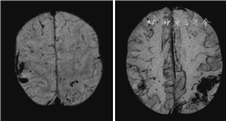

cSS指含铁血黄素在蛛网膜下腔、软脑膜和浅表皮质的沉积,在GRE或SWI序列上呈现沿脑沟分布的线样低信号(图3),有时在T2WI也可看到(图4)。如范围不超过3个脑沟,称为局灶性cSS,3个脑沟以上则称为播散性cSS,推测cSS最可能由cSAH所致[6, 30]。cSS对CAA的诊断具有较高特异度,在病理确诊的一组CAA(多数伴有脑出血)病例中其发生率可达60.5%,在经病理排除CAA的高血压脑出血对照组中则不存在[31]。在另一组pr-CAA病例中,cSS的发生率为40%,而在深部脑出血对照组中小于5%[32]。在鉴别脑出血和常染色体显性遗传脑动脉病伴皮质下梗死和白质脑病(cerebral autosomal dominant arteriopathy with subcortical infarcts and leukoencephalopathy)时,cSS是唯一有价值且对CAA高度特异的影像学标志[33]。在修订的“波士顿诊断标准”中,cSS、脑叶出血和微出血对CAA的诊断被赋予了同等意义[5]。cSS还是预测CAA未来脑出血风险的可靠指标,并且cSS的范围越大,脑出血的风险越高[34, 35, 36]。